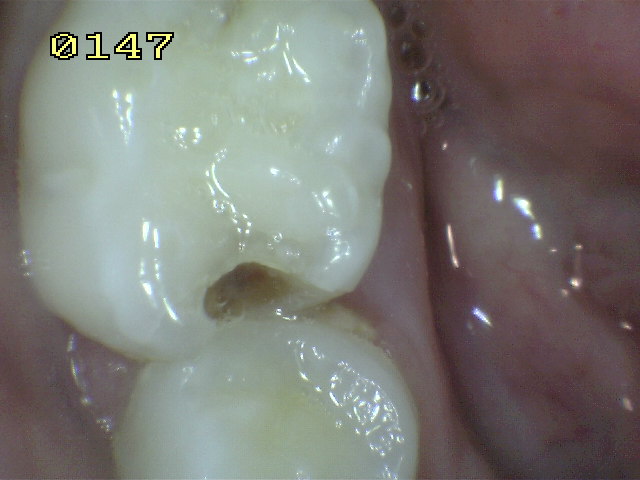

Código 5

(Caries Severa): Cavidad

detectable con dentina visible hasta la mitad de la superficie. |